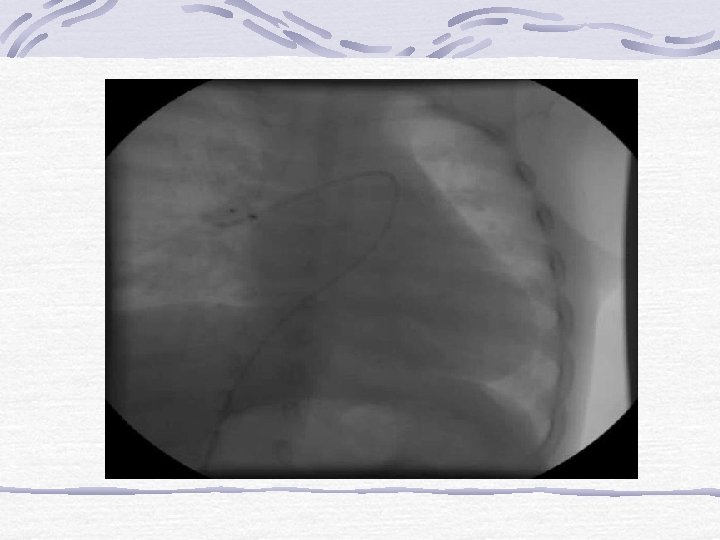

AORT KOARKTASYONU